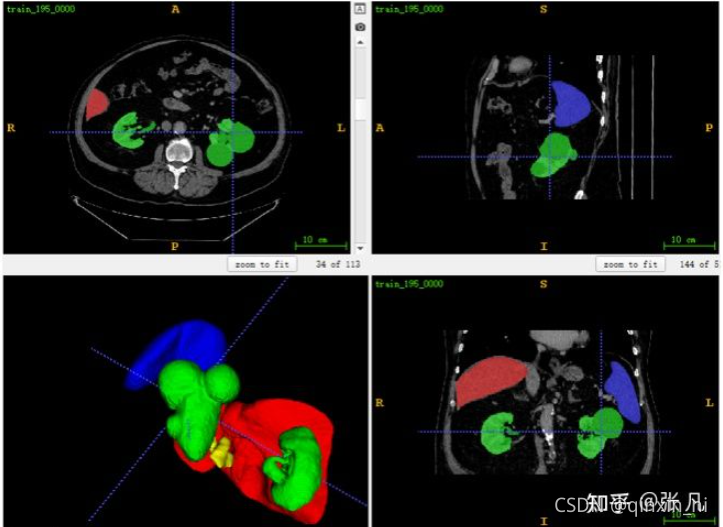

本文主要研究腹部CT扫描的多器官分割。如图所示,主要难点来自四个方面:

- 不同器官的视场、形状和大小的差异。

- 病变器官等异常可能导致分割失败。

- 多中心、多阶段、多厂商案例的数据源多样性。

- GPU内存大小有限,计算成本高。